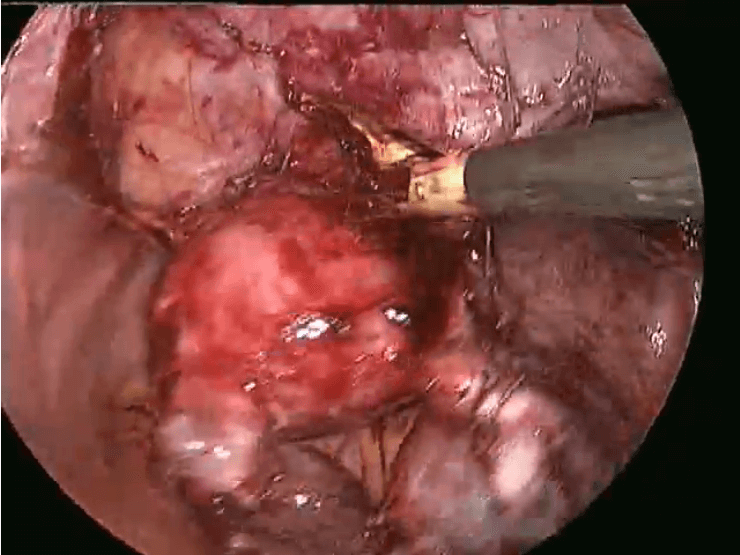

TLH IN ENDOMETRIOSIS - LIVE DEMONSTRATION